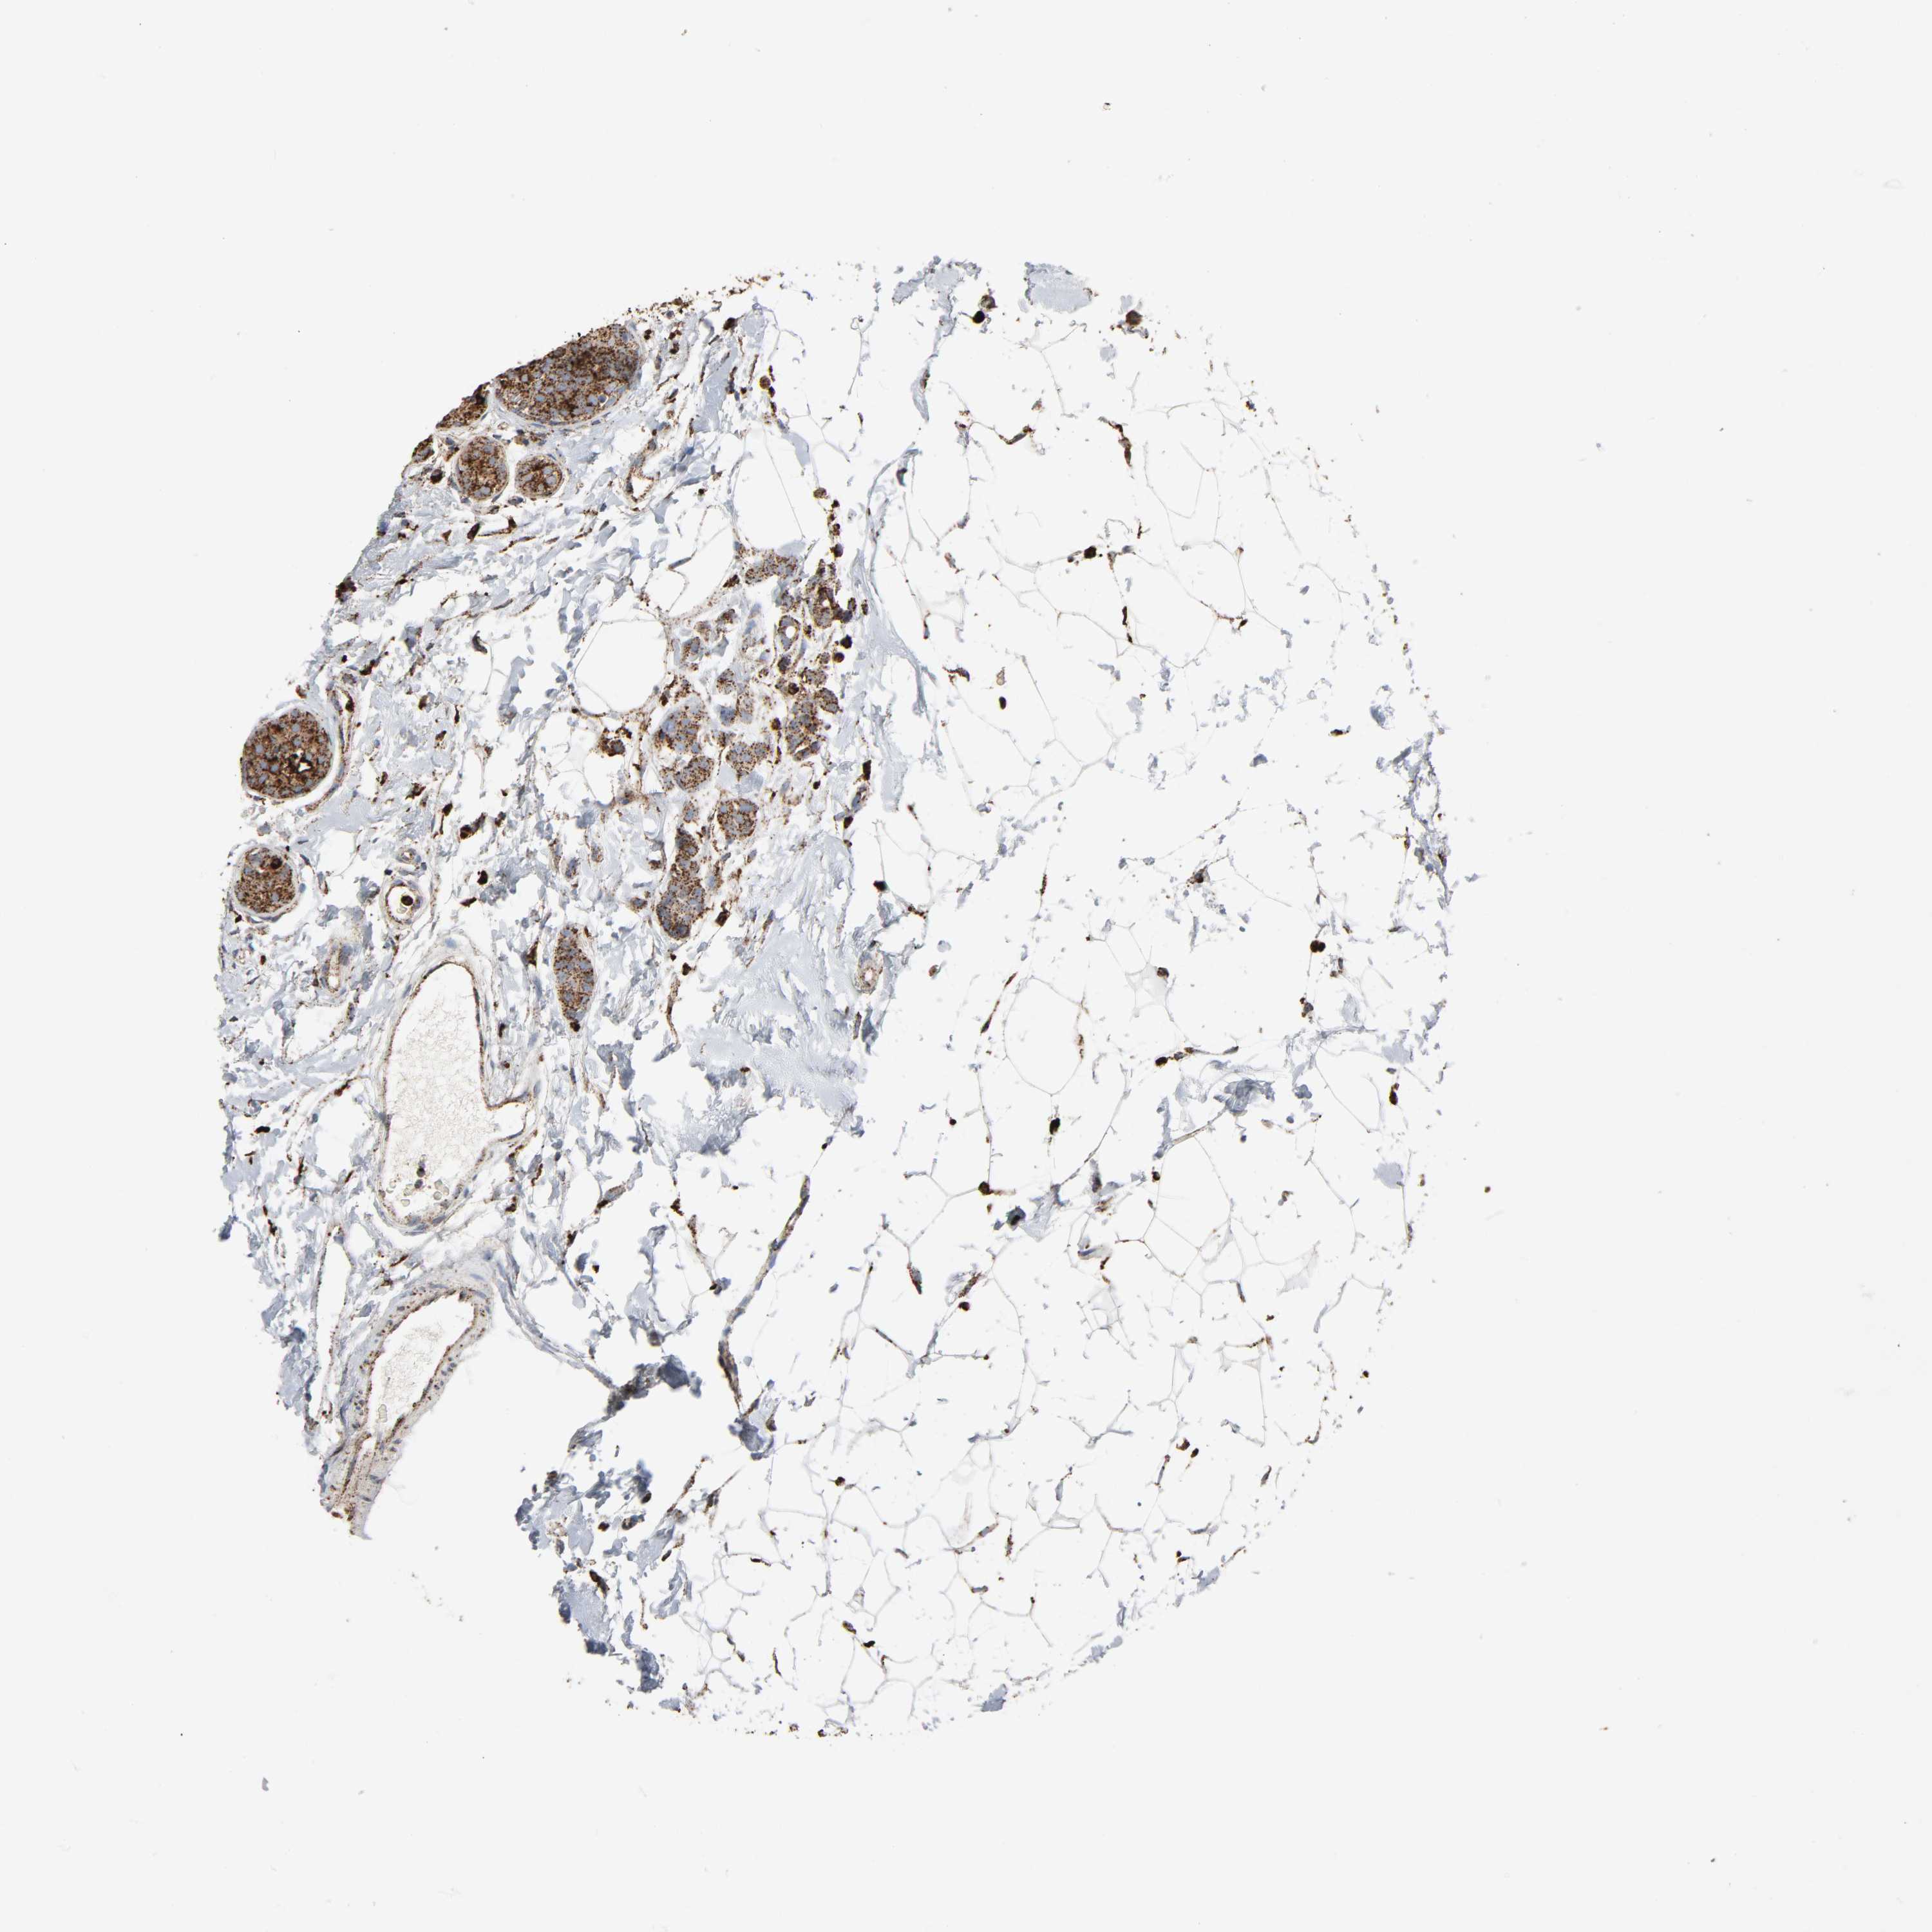

CANCER BREAST CANCER Show tissue menu

BRCA TCGA BRCA VALIDATION PROTEIN EXPRESSION